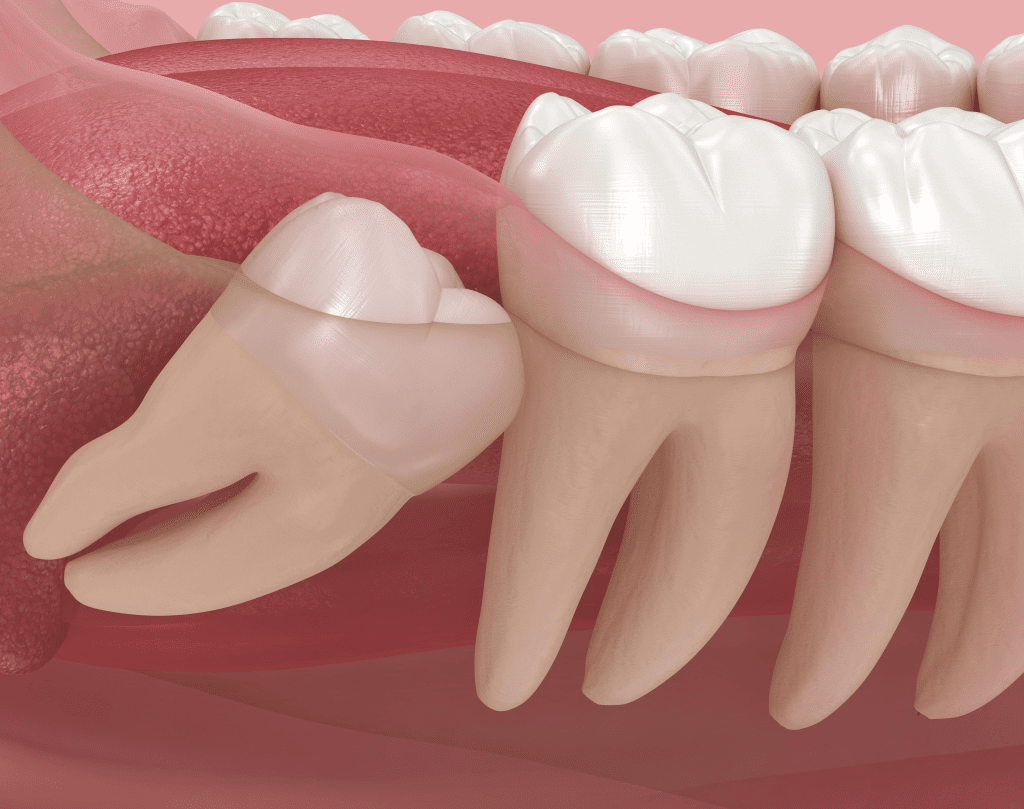

매복 사랑니 발치, 꼭 해야 할까 ? 치과 의사가 알려드립니다.

매복 사랑니 발치, 지금 뽑아야 할까, 기다려도 될까? 안녕하세요. 16년차 치과의사 장영준입니다. 이 글을 클릭하셨다면,아마 사랑니 때문에 고민이 있으실 가능성이 큽니다. 턱 뒤쪽이 뻐근하고,씹을 때 눌리는 느낌이 들고,음식물이 자꾸 끼고,입을

매복 사랑니 발치, 지금 뽑아야 할까, 기다려도 될까? 안녕하세요. 16년차 치과의사 장영준입니다. 이 글을 클릭하셨다면,아마 사랑니 때문에 고민이 있으실 가능성이 큽니다. 턱 뒤쪽이 뻐근하고,씹을 때 눌리는 느낌이 들고,음식물이 자꾸 끼고,입을

반갑습니다. 치의학 박사 장영준입니다. “사랑니 발치를 해야된다는데.. 너무 아플까 봐 걱정돼요..” 이 글을 읽으시는 분들은 안산사랑니치과 발치가 가능한 곳을 찾으시다가 이 글을 클릭해주셨을 것 같은데요.